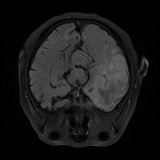

We obtain a subject-wise mean Dice score of 32.94% without any post-processing. By using a simple post-processing with erosion and dilation with filters, this number improves to 48.20% mean Dice score. In comparison, a similar study conducted by [3] consisting of a multitude of algorithms including AnoVAEGAN [4] and f-AnoGANS, obtained a best mean score of 27.8% Dice after post-processing by f-AnoGANS. Before post-processing the best method was Constrained AutoEncoder [8] with a score of 9.7% Dice. An exhaustive list is presented in Table 1. Figure 4 shows sample images of our results.

We obtain a subject-wise mean Dice score of 63.67% for the brain tumor segmentation. Utilizing a simple post-processing scheme of erosion and dilation with filter, we improve our mean Dice score to 68.01%. Figure 4 shows samples generated by our ASC-Net and Table 2 shows our before and after post-processing results. We attempted to apply f-AnoGANs [34] by following their online instructions and failed to generate good reconstructions as shown in Figure 5. The failure of AnoGANs in the reconstruction brings to light the issue with the regeneration based methods and the complexity and stability of GAN-based image reconstruction.